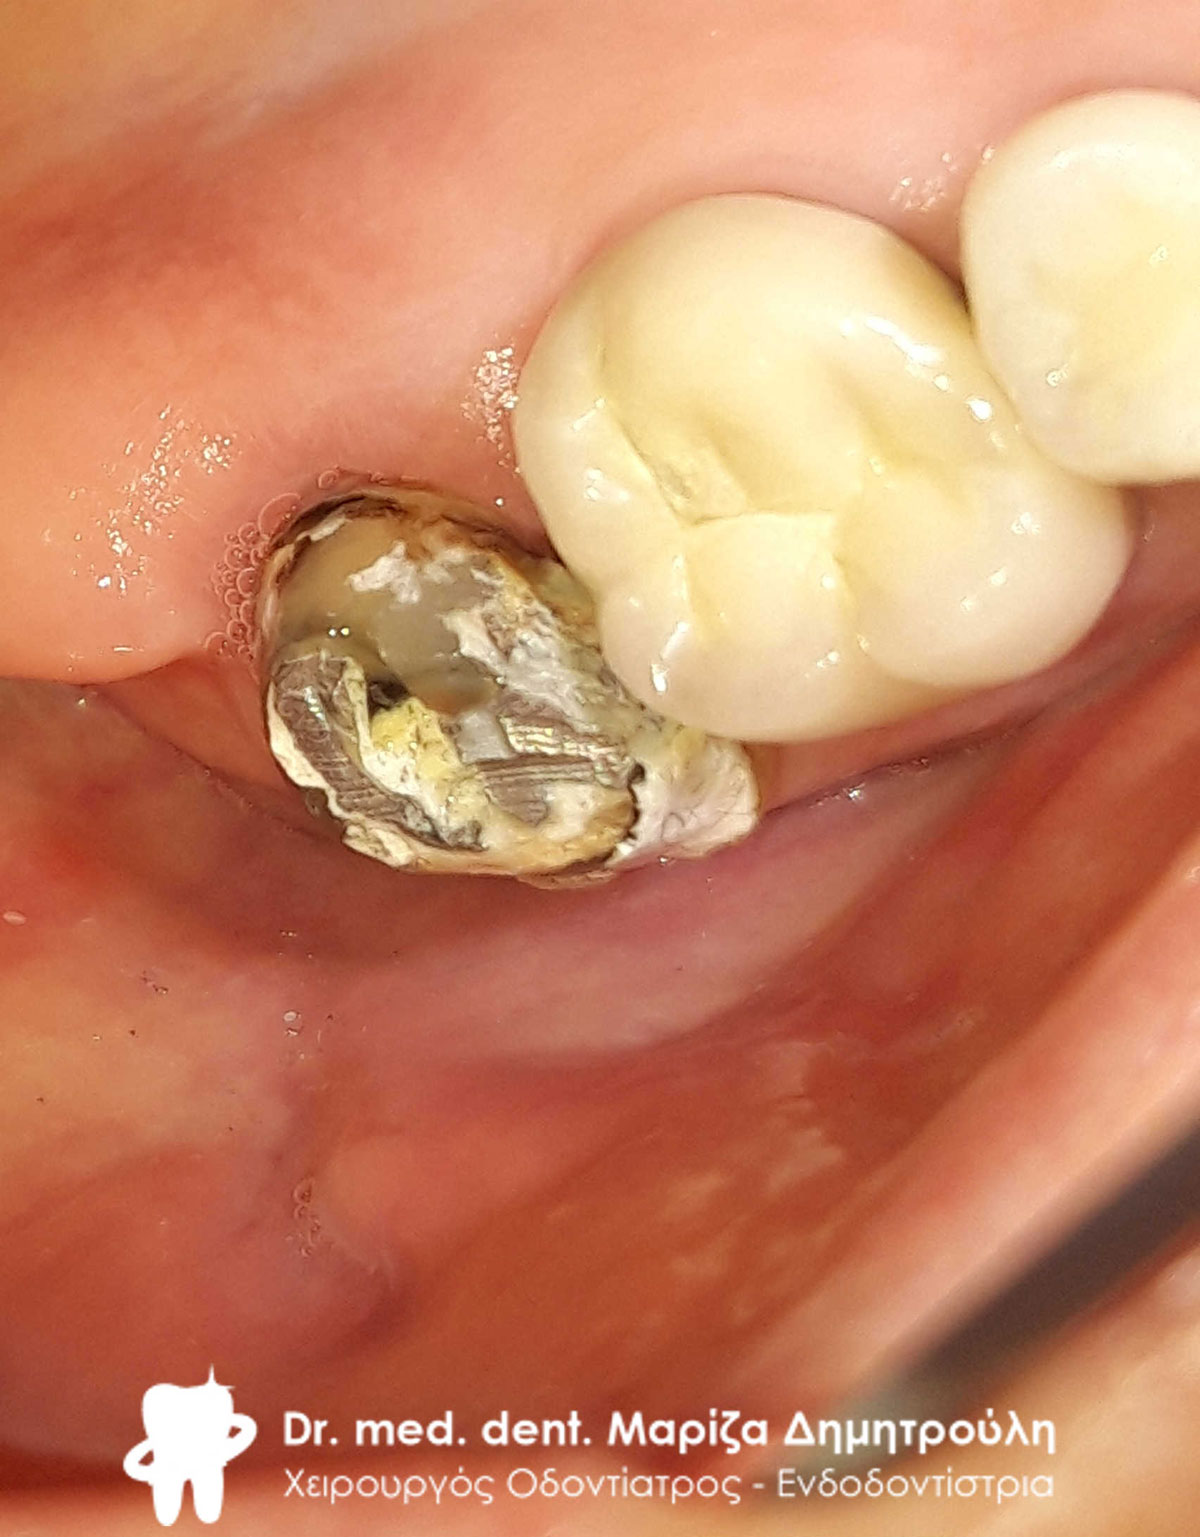

Αρχική εικόνα των δοντιών μετά την αφαίρεση της παλιάς γέφυρας

Τα δόντια μετά τις απαραίτητες απονευρώσεις και τις ανασυστάσεις